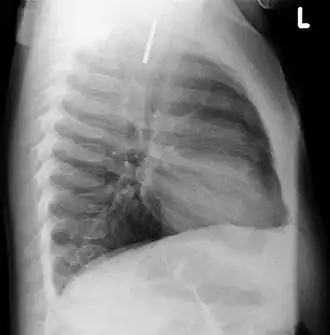

Multiple button batteries in the stomach -

Button battery in the stomach

Both children and adults experience problems caused by foreign objects becoming lodged within their bodies. Young children, in particular, are naturally curious and may intentionally put shiny objects, such as coins or button batteries, into their mouths. They also like to insert objects into their ear canals and nostrils.[1] The severity of a foreign body can range from unconcerning to a life-threatening emergency. For example, a coin causes local pressure on the tissue but generally is not a medical emergency to remove. A button battery, which can be a very similar size to a coin, generates hydroxide ions at the anode and causes a chemical burn in two hours.[2] An ingested button battery that is stuck in the esophagus is a medical emergency. In 2009, Avolio Luigi and Martucciello Giuseppe showed that although ingested nonmagnetic foreign bodies are likely to be passed spontaneously without consequence, ingested magnets (magnetic toys) may attract each other through children's intestinal walls and cause severe damage, such as pressure necrosis, perforation, intestinal fistulas, volvulus, and obstruction.[3]